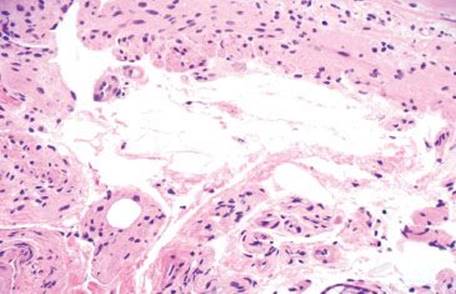

Figure 4.253 Lipoma. In contrast to air artifacts, lipomas show cohesion of the lesional cells. There are few intervening stromal cells or inflammatory cells present, helpful distinguishing features of a lipoma.

Figure 4.254 Lipoma. High power shows that each lipocyte has its own small, peripheral nucleus. Also the (benign) neoplastic cells have a uniform architecture with few intervening nonlipocytic elements. These key features of a lipoma contrast with findings in air artifacts.